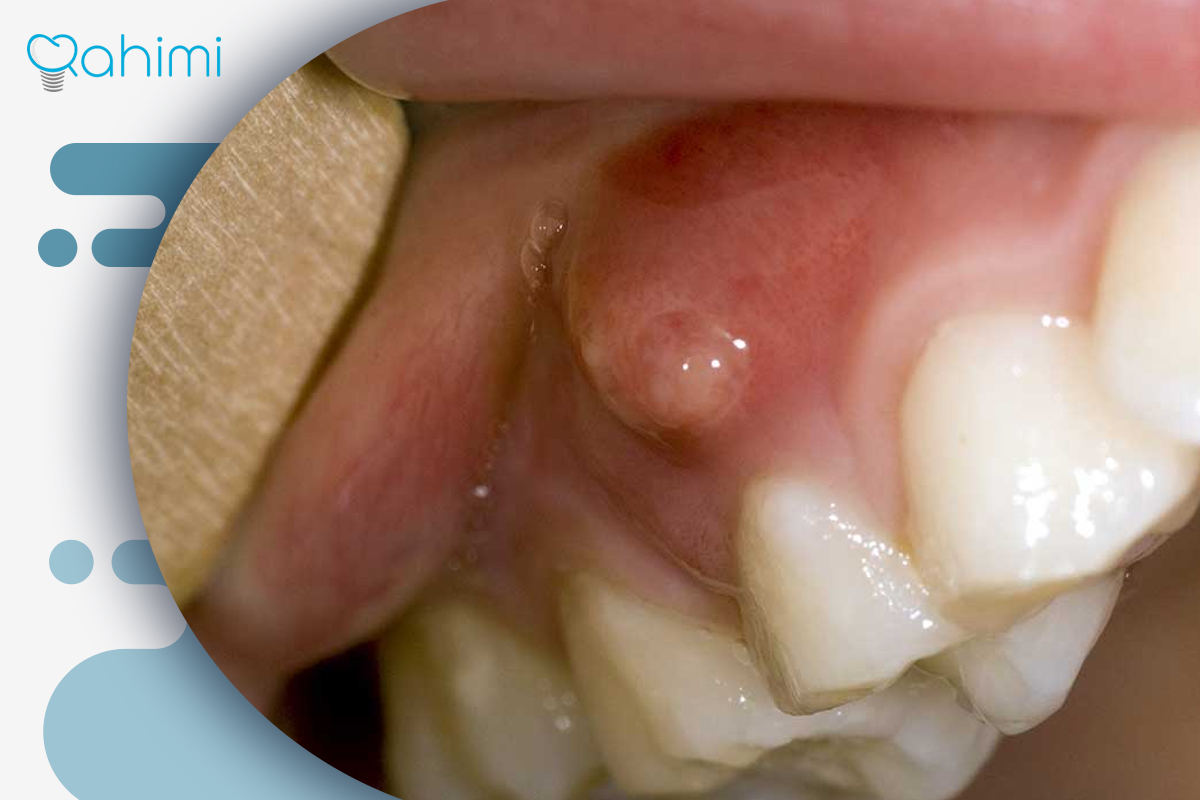

آبسه لثه: آبسه لثه یکی از شایعترین انواع جوش سفید روی لثه است که در اثر نفوذ باکتریها به فضای بین دندان و لثه ایجاد میشود. این نوع عفونت معمولاً بهصورت برآمدگی سفید پر از چرک ظاهر میشود و با درد، التهاب و گاهی بوی بد دهان همراه است. در صورت عدم درمان، چرک میتواند به بافتهای اطراف گسترش یافته و به تحلیل لثه یا حتی از بین رفتن استخوان فک منجر شود. دکتر رحیمی با بهرهگیری از روشهای جراحی دقیق و درمانهای ضدباکتریایی پیشرفته، آبسه را تخلیه و محیط دهان را به حالت سالم بازمیگرداند.

موکوسل: موکوسل یا کیست بزاقی زمانی ایجاد میشود که یکی از غدد بزاقی کوچک دهان دچار انسداد شود و مایع در آن جمع گردد. این ضایعه معمولاً به شکل برآمدگی نرم و شفاف یا سفید روی لثه یا لب داخلی دیده میشود. موکوسل معمولاً دردناک نیست، اما در صورت افزایش اندازه، ممکن است در خوردن یا صحبت کردن اختلال ایجاد کند.